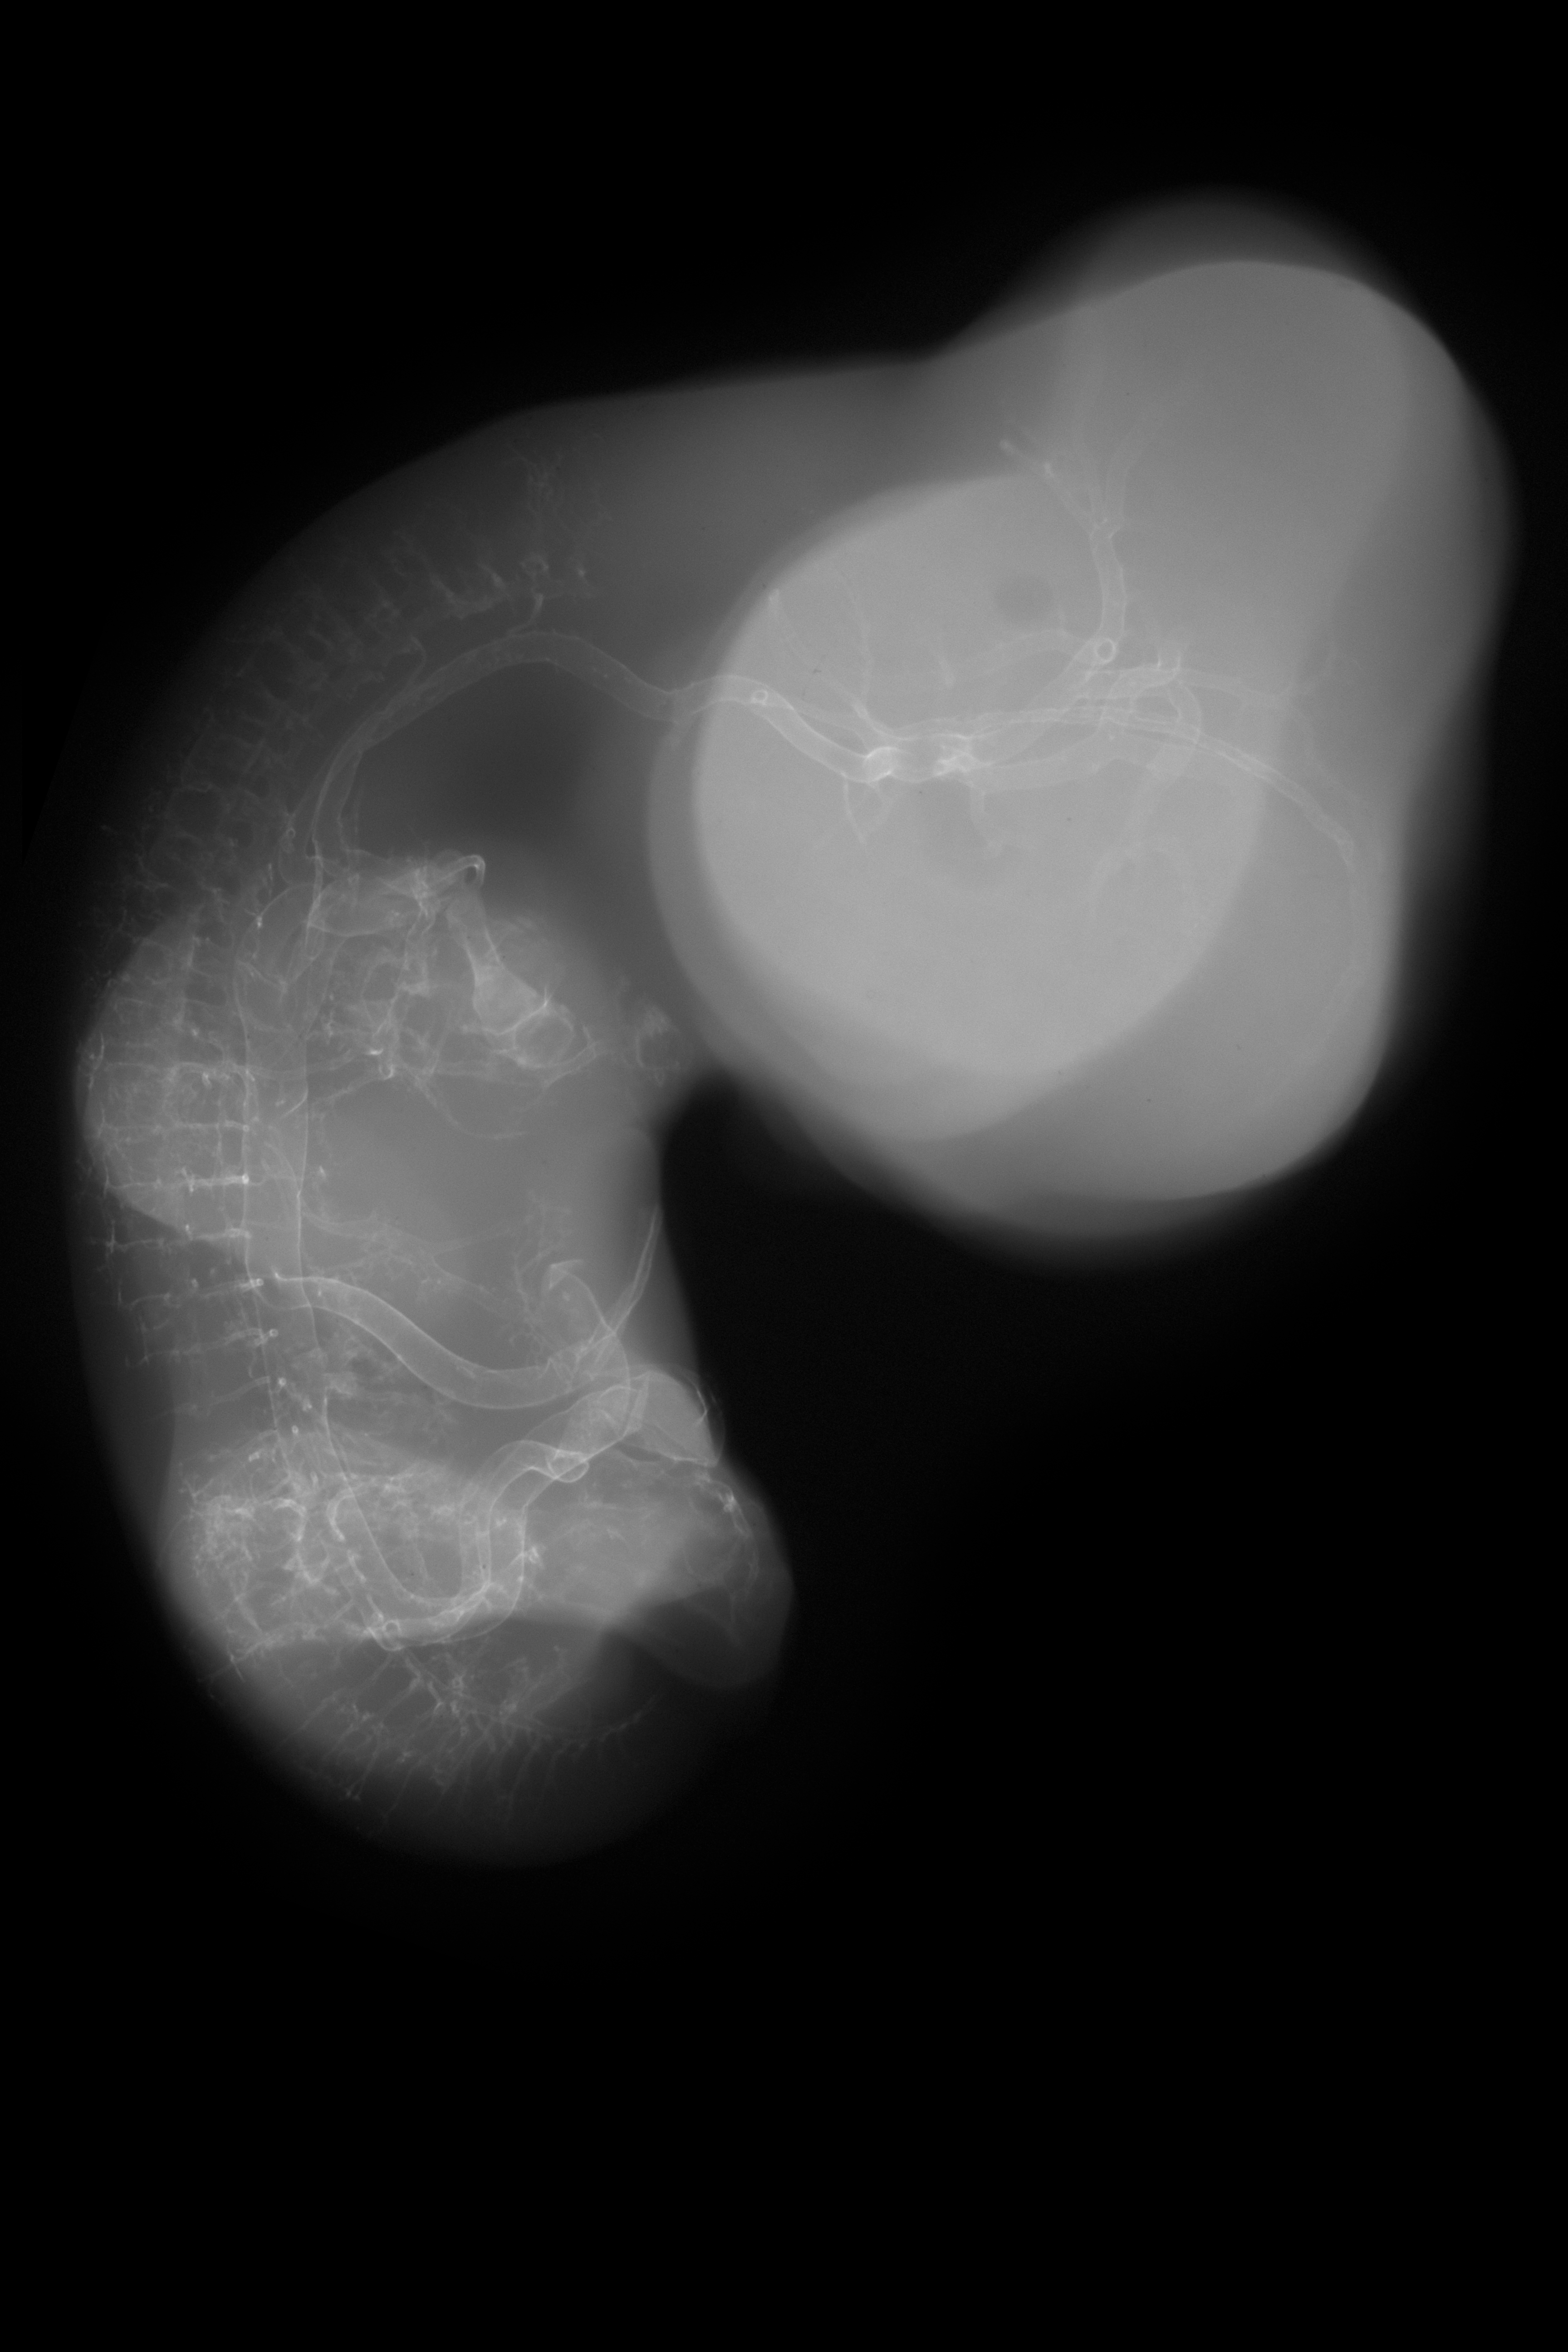

Chick Embryo Microangiography

Hamburger-Hamilton (HH) Stage 29 (approx. 6 - 6.5 days)

Stereo X-Ray Micrographs